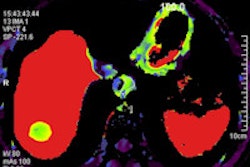

While you're in the community, check out our article on a mysterious decline in nuclear myocardial perfusion imaging (MPI) studies within the Kaiser Permanente healthcare system. MPI scans dropped by half in five years, but Kaiser's status as an integrated delivery network means the usual economic reasons for such a decline -- such as reimbursement cuts -- aren't a factor. Read the story by clicking here, or visit our Molecular Imaging Digital Community at molecular.auntminnie.com.